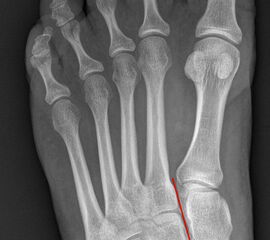

Auf den dp-Aufnahmen sollte der mediale Rand der Metatarsale-2-Basis mit dem medialen Rand des Os cuneiforme intermedium eine homogene Linie ohne Stufenbildung bilden (Abb. 7+8). Außerdem ist auf den Abstand zwischen der Metatarsale-1- und -2-Basis zu achten. Dieser sollte nicht größer als 2 mm bzw. im Vergleich zur Gegenseite nicht mehr als 1 mm erweitert sein. In bis zu 90% der Fälle zeigt sich ein sogenanntes „Fleck sign“ (Abb. 9), ein knöchernes Fragment zwischen der Metararsale-1- und -2-Basis im Sinne eines knöchernen Ausrisses des Lisfranc-Ligaments an der Metatarsale-2-Basis 211936410. Oft liegen zusätzliche Frakturen der Metatarsalebasen oder der Tarsale vor, die ebenfalls identifiziert werden sollten. Bei jeder Mittelfußbasisfraktur sollte umgekehrt an eine Lisfranc-Verletzung gedacht werden.

Zum Lesen der Bildbeschreibung und zur Vollansicht bitte die Bilder anklicken.